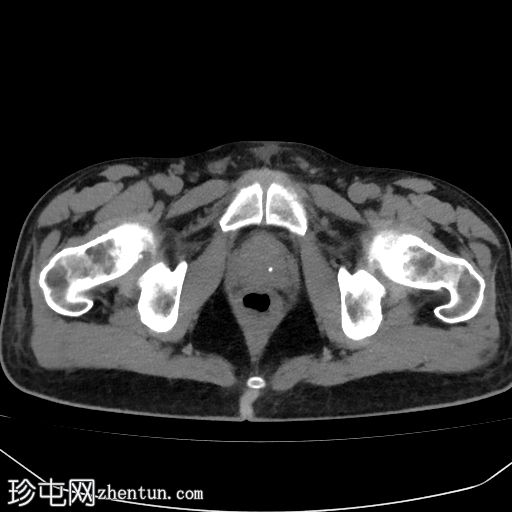

腹部(肝脏)CT

轴位

平扫

轴位增强扫描

延迟期

肝硬化征象包括表面和实质结节、实质异质性、右后肝切迹征和容积重分布。

门静脉可见肿瘤血栓,表现为血栓强化。

肝脏可见无数细小病灶,动脉期呈非环状强化,门静脉期呈消退,提示弥漫性肝细胞癌。

其他发现包括腹水和左侧肾上腺可疑增厚。